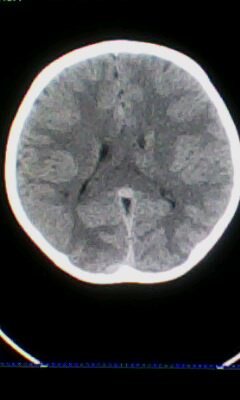

标题: PED3324:男 10岁 右侧 眼不自主抽动 自感颈部不适 [打印本页]

标题: PED3324:男 10岁 右侧 眼不自主抽动 自感颈部不适

蛛网膜下腔出血。

蛛网膜下腔出血可能。

颅脑ct轴位平扫颅内未见明确异常;建议必要时行mri检查。

窗调的不好,图像感觉怪怪的,不好说有什么明显异常,可建议mri检查。

颅脑ct轴位平扫颅内未见明确异常。